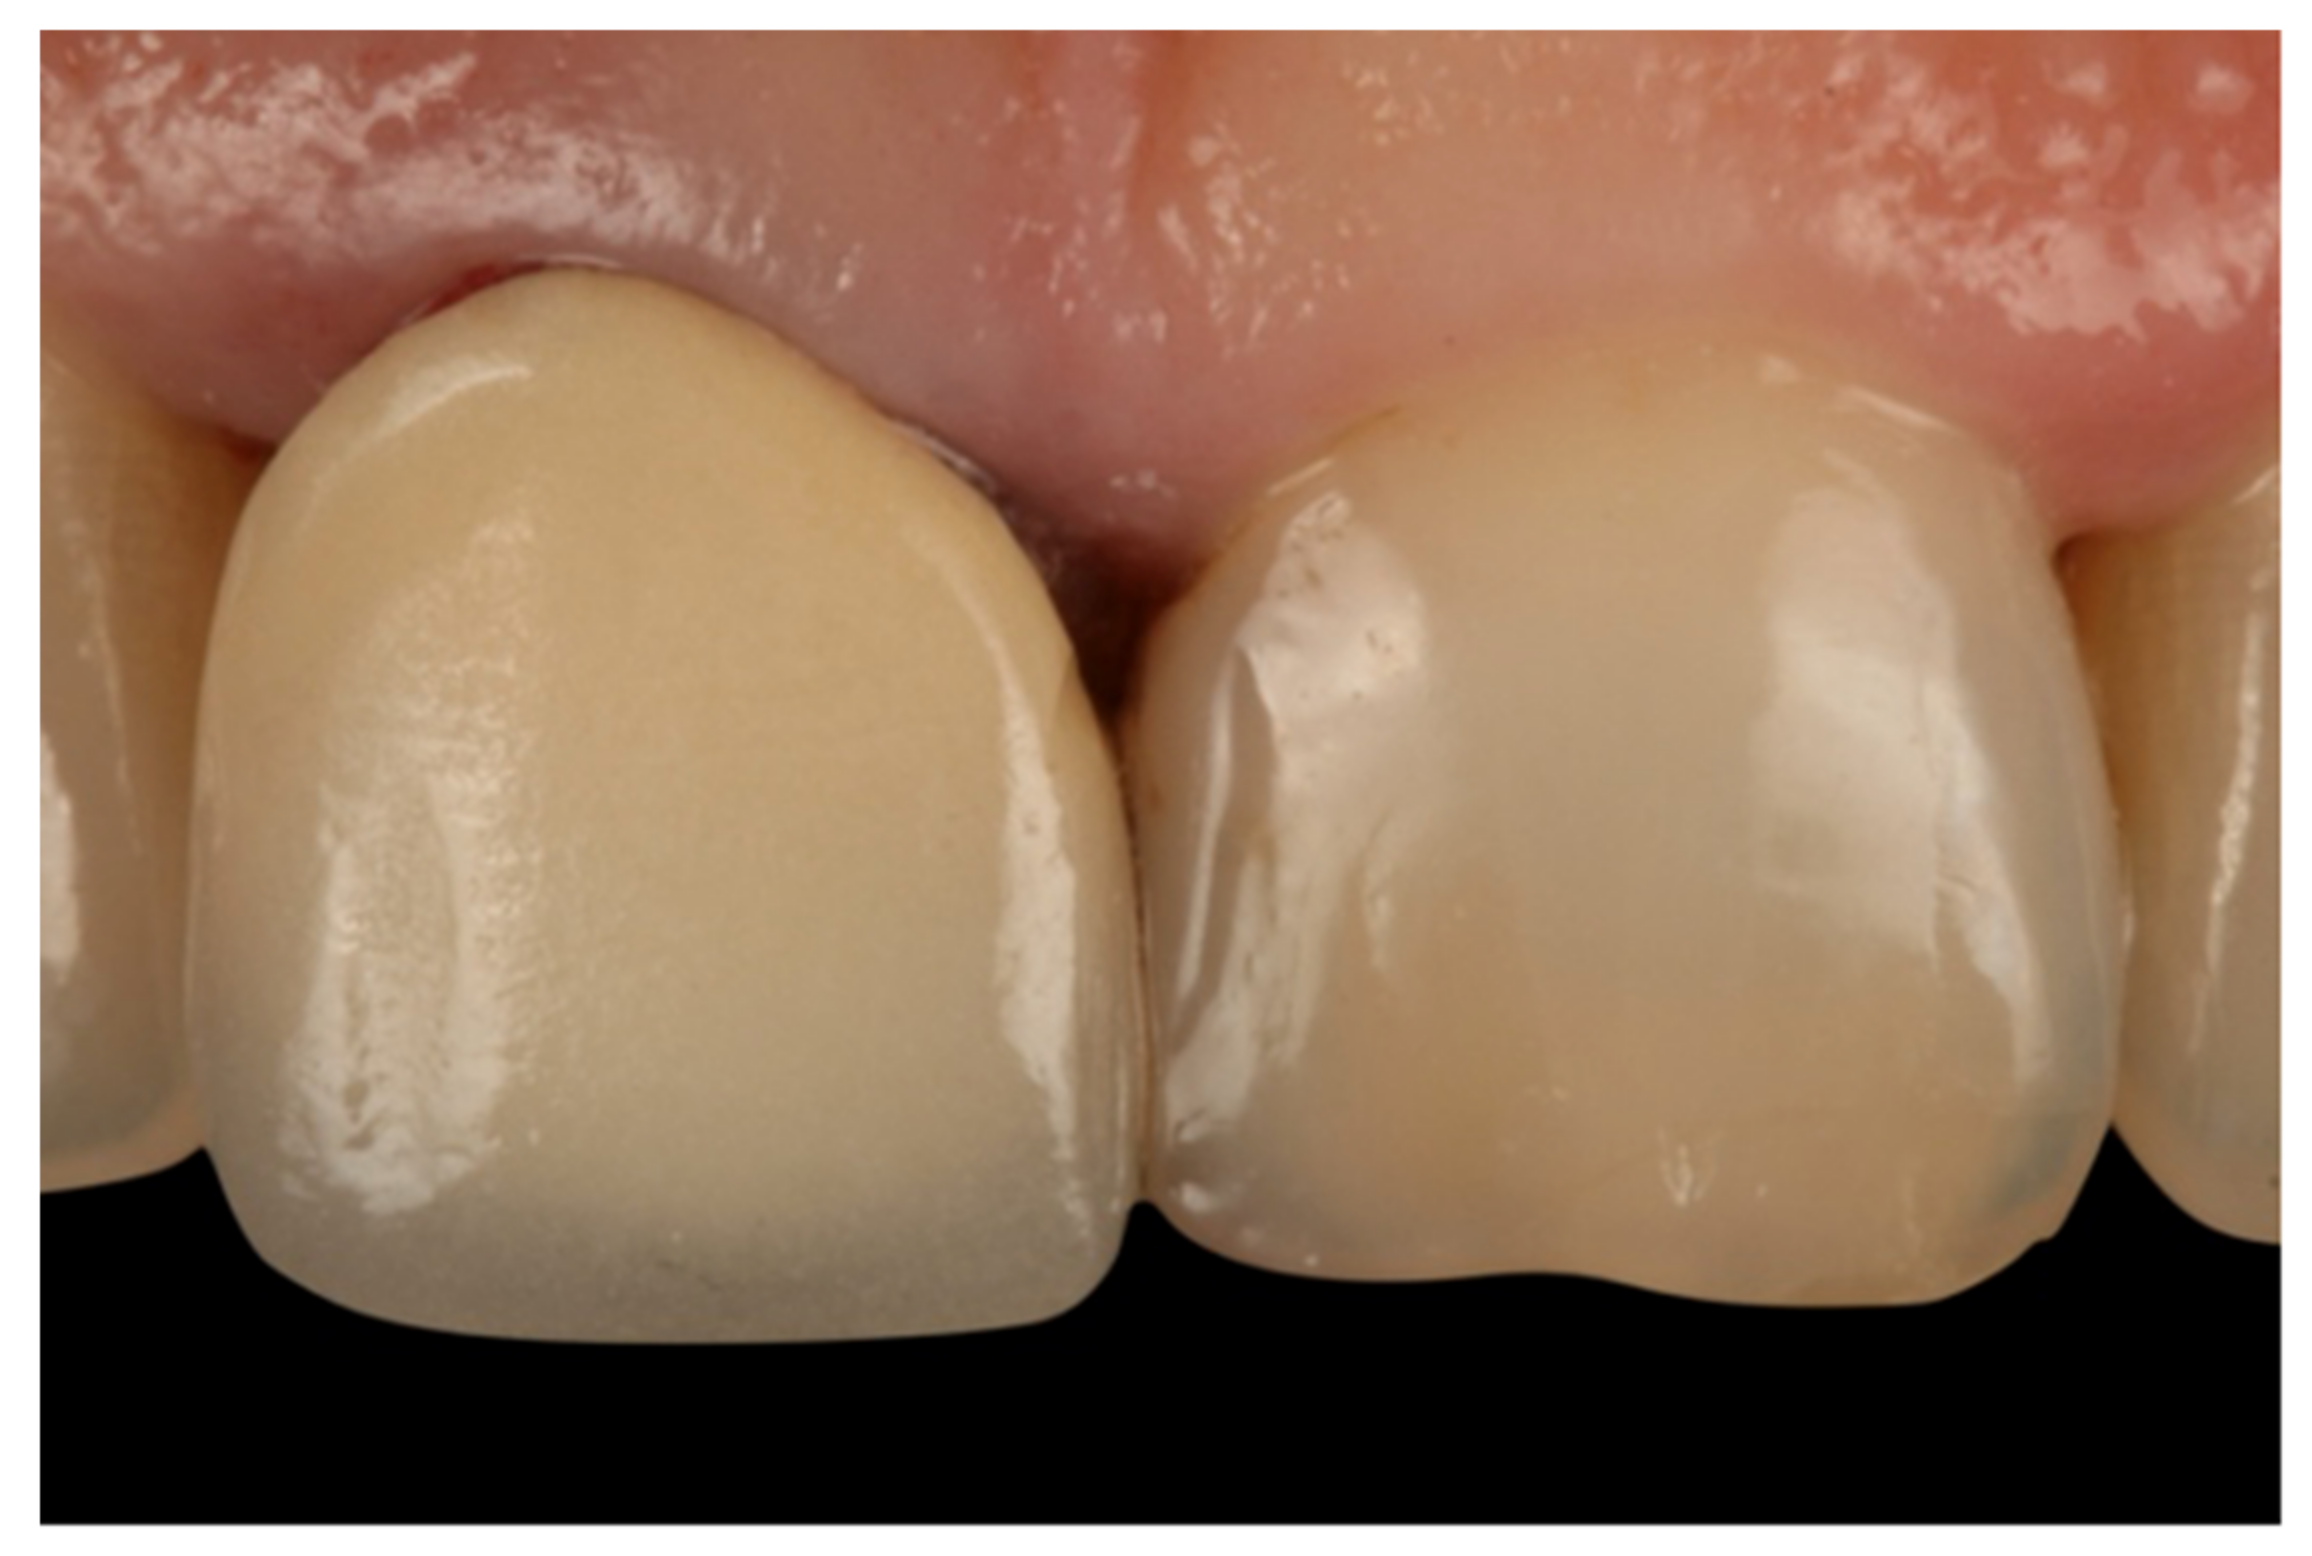

- Teeth treated with this technique presented improved plaque indices, stable probing depths, increased gingival thickness, and stable gingival margins over the 6-year follow-up.

- Treatment with a fixed prosthesis using the BOPT technique has a positive impact on patient satisfaction, especially in cases concerning the re-treatment of old fixed prostheses. This fact is due to the esthetic improvement not only of the restoration but also of the surrounding tissues, as it improves gingival quality by thickening the tissue, thus preventing gingival recession.

- Agustín-Panadero, R.; Serra-Pastor, B.; Fons-Font, A.; Solá-Ruíz, M.F. Prospective Clinical Study of Zirconia Full-coverage Restorations on Teeth Prepared with Biologically Oriented Preparation Technique on Gingival Health: Results After Two-year Follow-up. Oper. Dent. 2018, 43, 482–487. [Google Scholar] [CrossRef] [PubMed]